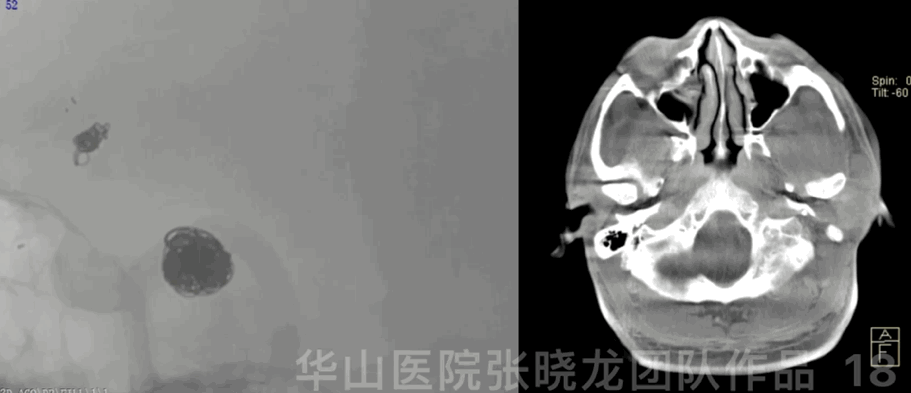

图 18 GIF. 弹簧圈成篮。Dyna-CT未见出血。

图 19. 立即行头颅CT,未见出血。予半量肝素化。

Figure 21. Post-operative day 2 head CT showed no hemorrhage and DWI depicted right cerebellum, midbrain and left basal ganglia region acute infarction with bilateral hemisphere scattered infarction.

图 21. 术后第2天头颅CT未见出血,DWI提示右侧小脑半球、中脑及左侧基底节区急性脑梗,双侧大脑半球散在梗死。